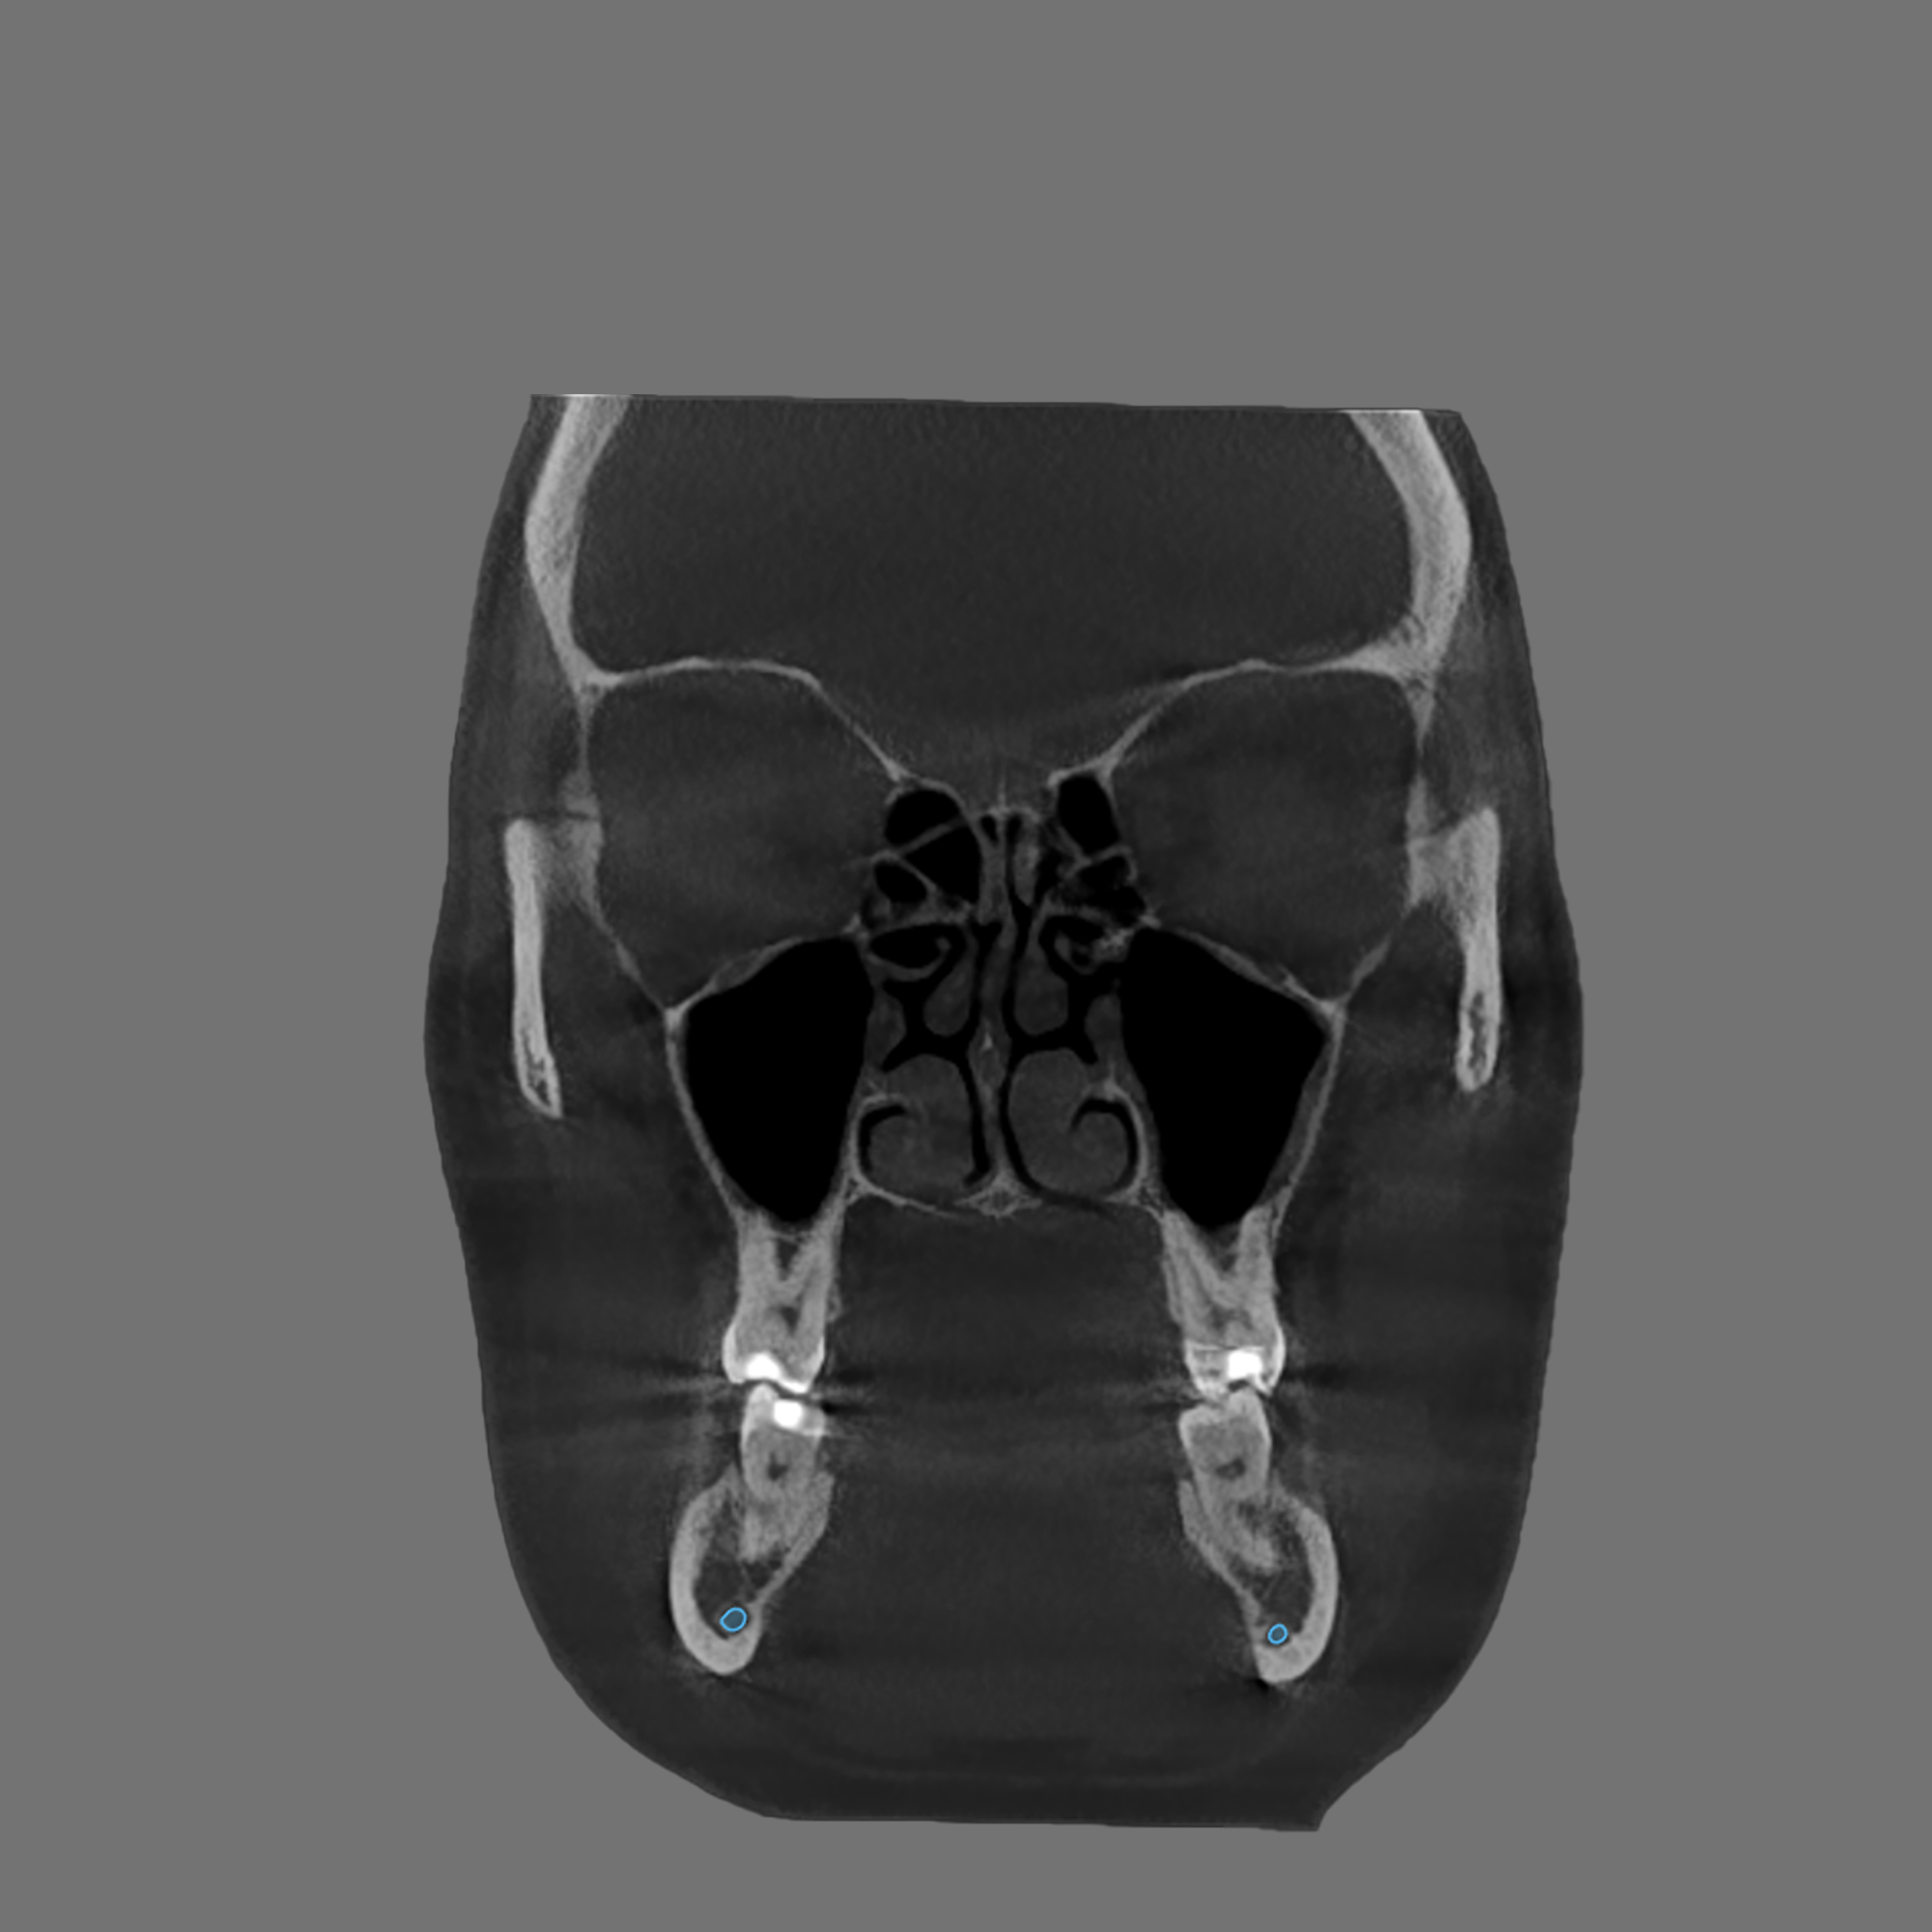

Your evaluation includes a CT scan, comprehensive oral images, sleep assessment, and personalized treatment plan from Dr. Trivedi. If you choose to proceed with the complete solution stack, your evaluation costs will be applied as a discount.

After your evaluation, the doctor reviews your results and explains how your airway structures are impacting your health. You’ll then receive a personalized plan that may include palatal expansion, aligners, or other therapies to optimize your health.